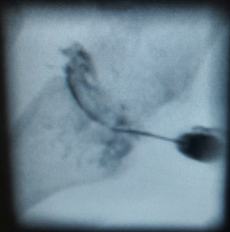

Unter Durchleuchtung wird bei der RSO mittels einer Nadel ein radioaktiver Stoff in den Gelenkspalt injiziert. Die Substanz verödet dann die Gelenkschleimhaut und reduziert oder beendet den Schmerz im Gelenk.